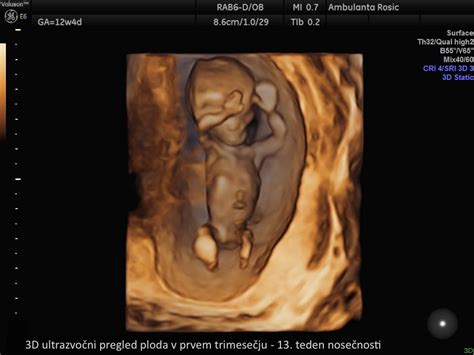

Prvo trimesečje (1.-13. teden)

V prvih tednih nosečnosti se telo nosečnice intenzivno prilagaja na rast novega življenja. To obdobje je pogosto zaznamovano z občutki utrujenosti, slabosti in občutljivostjo prsi. Medtem ko se telo matere prilagaja, se v tem času intenzivno oblikuje zarodek in razvijajo osnovni organi. Prvi ultrazvočni pregled običajno poteka med 7. in 10. tednom nosečnosti, s čimer se potrdi nosečnost in oceni njeno zgodnje napredovanje.